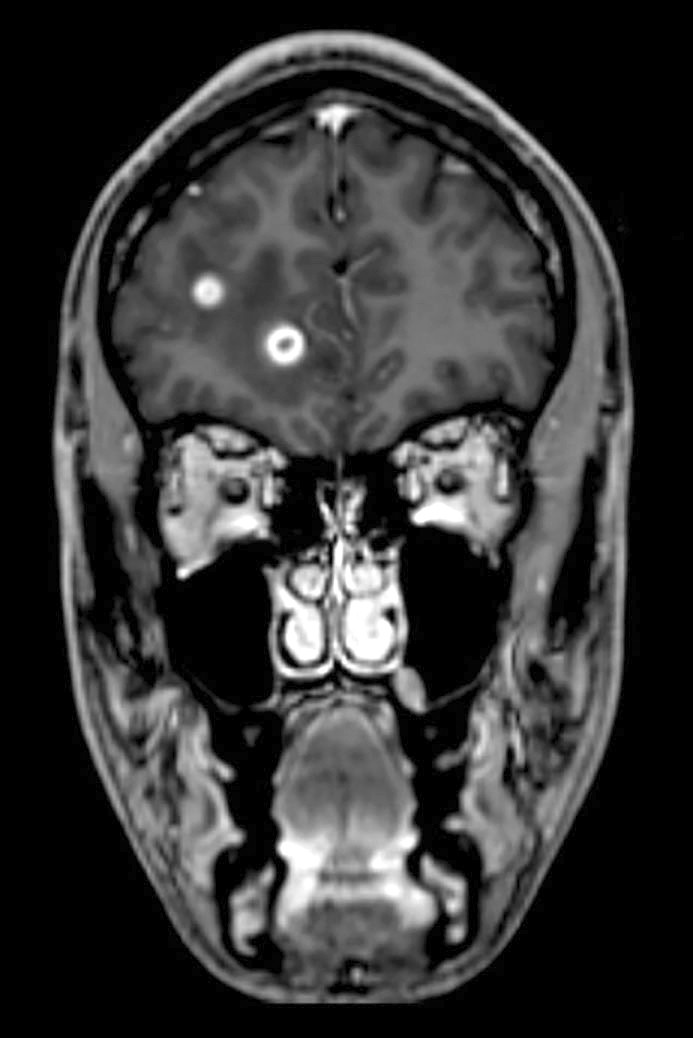

CT-undersøkelse uten kontrast av hodet ble tatt umiddelbart etter innleggelse og viste lavattenuerende forandringer i hvit substans frontalt i høyre storhjernehemisfære (fig 1) og i høyre lillehjernehemisfære. Supplerende magnetisk resonanstomografi av hjerne og medulla påfølgende dag avdekket multiple lesjoner i hjernestamme, lillehjerne og begge storhjernehemisfærer (fig 2). Nevroradiolog vurderte funn som forenlig med multiple metastaser, hjernetuberkulose, parasittsykdom eller septiske embolier med sekundær abscessdanninger. Spinalvæskeundersøkelse viste leukocyttnivå på 9 · 109/l, men ellers normale verdier for erytrocytter, glukose og protein. Det ble samme kveld utført CT av thorax, abdomen og bekken for å se etter tegn til ekstracerebral sykdom, inkludert kreft, bakterielt infeksjonsfokus, tuberkulose i eller utenfor lunger, eventuelt tegn til parasittsykdom. Denne avdekket multiple mikronoduli i lungene, mest i apikale deler av begge overlappene, én litt større nodulus apikalt og lateralt i venstre overlapp samt en liten høyattenuerende lesjon til høyre for avgangen av høyre hovedbronkus som var forenlig med en forkalket lymfeknute (fig 3). Det var multiple lavattenuerende lesjoner i abdomen og bekken, mest i øvre del av lever, og i tillegg lesjoner i nyre og prostata. Radiologen beskrev funnene som mest forenlig med miliær tuberkulose.